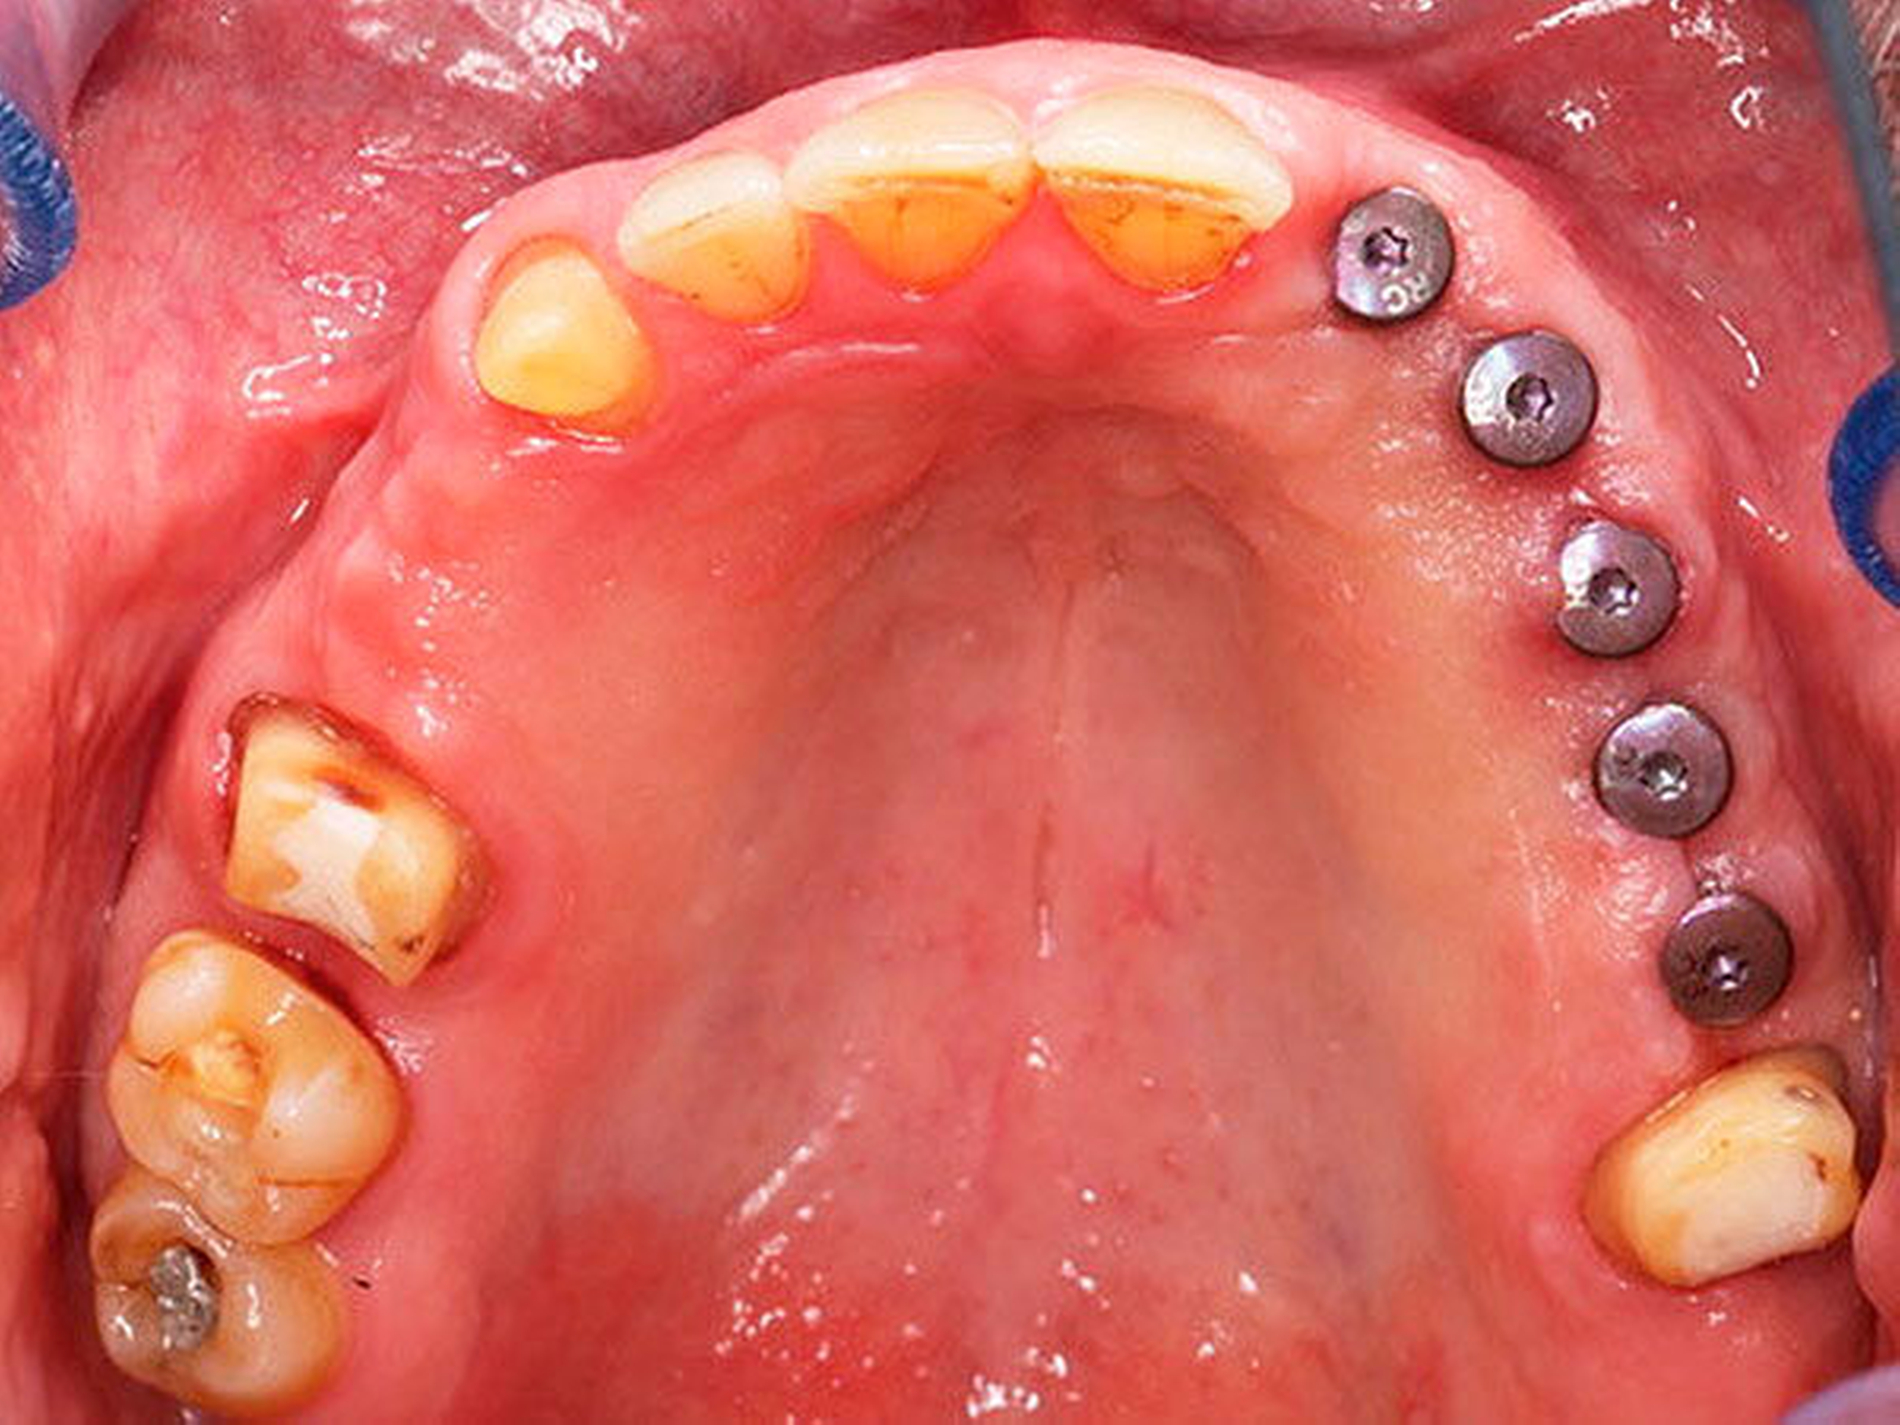

Die chirurgische Platzierung von Zahnimplantaten, das heißt die eigentliche Implantation, und die nachfolgende prothetische Versorgung dieser Implantate liegen nicht immer in einer Hand, sondern werden zum Teil von zwei verschiedenen Behandlern durchgeführt. Eine solche Arbeitsteilung hat durchaus Vorzüge: Aus der Allgemeinchirurgie wissen wir, dass Operateure mit großer Behandlungsroutine (hohe Fallzahlen pro Jahr) signifikant bessere Ergebnisse erzielen [Halm et al., 2002]. Doch geteilte Zuständigkeiten bergen auch Fallstricke: Wenn die Implantation und die nachfolgende prothetische Versorgung nicht gemeinsam geplant oder zumindest aufeinander abgestimmt werden, stellen sich im Fall eines ungünstigen Endresultats (Behandlungsfehler-Vorwurf) Fragen der Verantwortlichkeit. Man denke etwa an einen Fall, in dem ein Fachchirurg Implantate setzt, die aus Sicht des Implantatprothetikers falsch positioniert sind (Abbildungen 1, 2, 4, 5 und 6).

Letzterem bleibt nur die Wahl zwischen der Ablehnung der Weiterbehandlung und der Empfehlung einer aufwendigen und substanzverlustträchtigen Revision der Implantate (beides mutet dem betroffenen Patienten einiges zu) oder einer „Kompromissbehandlung“ mit dem Ziel, die invasive Revision der gesetzten Implantate abzuwenden und so den Schaden für den Patienten zu begrenzen. Heikel wird es insbesondere dann, wenn der Prothetiker in bester Absicht eine solche Kompromissbehandlung wagt, diese sich aber als nicht alltagstauglich erweist und der Patient schlussendlich Klage erhebt.

Hier kann es unter Umständen schwerfallen, die Verantwortung zuzuweisen: Liegt die Schuld beim Chirurgen, der die Implantate an ungünstiger Stelle gesetzt hat, oder beim Prothetiker, der sich nolens volens auf diese Situation eingelassen und ein letztlich unzureichendes Behandlungsergebnis erzielt hat? Aus fachlicher und ethischer Sicht ist die eigentliche Ursache für das insuffiziente Behandlungsergebnis beim Chirurgen zu suchen. Juristisch gesehen trägt dagegen jedoch der Implantatprothetiker die unmittelbare Verantwortung für das Behandlungsergebnis, da er die insuffiziente Suprakonstruktion geplant und eingegliedert hat. Rechtlich verhängnisvoll wird dieses Vorgehen insbesondere dann, wenn er den Patienten nicht explizit über den Kompromiss- und Versuchscharakter seiner Versorgung aufgeklärt hat oder das Aufklärungsgespräch und das Einverständnis des Patienten zur eigenen juristischen Absicherung nicht sorgsam dokumentiert hat.